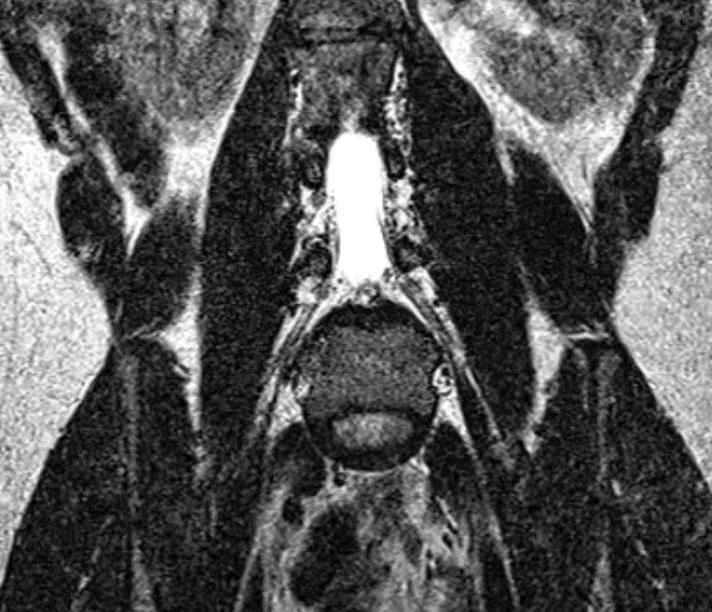

Magnetic Resonance Imaging (MRI)

The Siemens 3T Verio MRI scanner comprises a 70cm diameter open-bore, short-axis magnet. It has been equipped with a comprehensive range of transmit/receive coils suitable for many body regions and applications. The relatively large bore (compared to most MRI systems) ensures a higher degree of subject comfort and compliance.